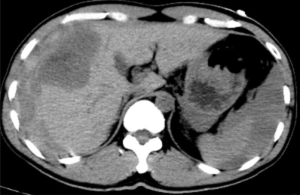

據悉,患者既往有多年乙型肝炎病史,突發右上腹劇烈疼痛入院。患者入院時血壓70/40mmHg,心率110次/分,全腹壓痛。血常規血紅蛋白87g/L,甲胎蛋白>1210 ng/ml。腹部B超檢查及CT平掃檢查示“肝腫瘤并出血,腹腔積血積液”。